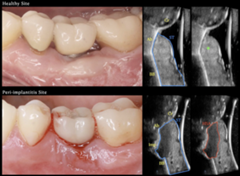

Barootchi S, Tavelli L, Majzoub J, Chan HL, Wang HL, Kripfgans OD. Ultrasonographic Tissue Perfusion in Peri-implant Health and Disease. J Dent Res. 2022;101(3):278-285. doi:10.1177/00220345211035684. |

Galarraga-Vinueza ME, Barootchi S, Mancini L, et al. Echo-intensity characterization at implant sites and novel diagnostic ultrasonographic markers for peri-implantitis. J Clin Periodontol. Published online April 1, 2024. doi:10.1111/jcpe.13976. |